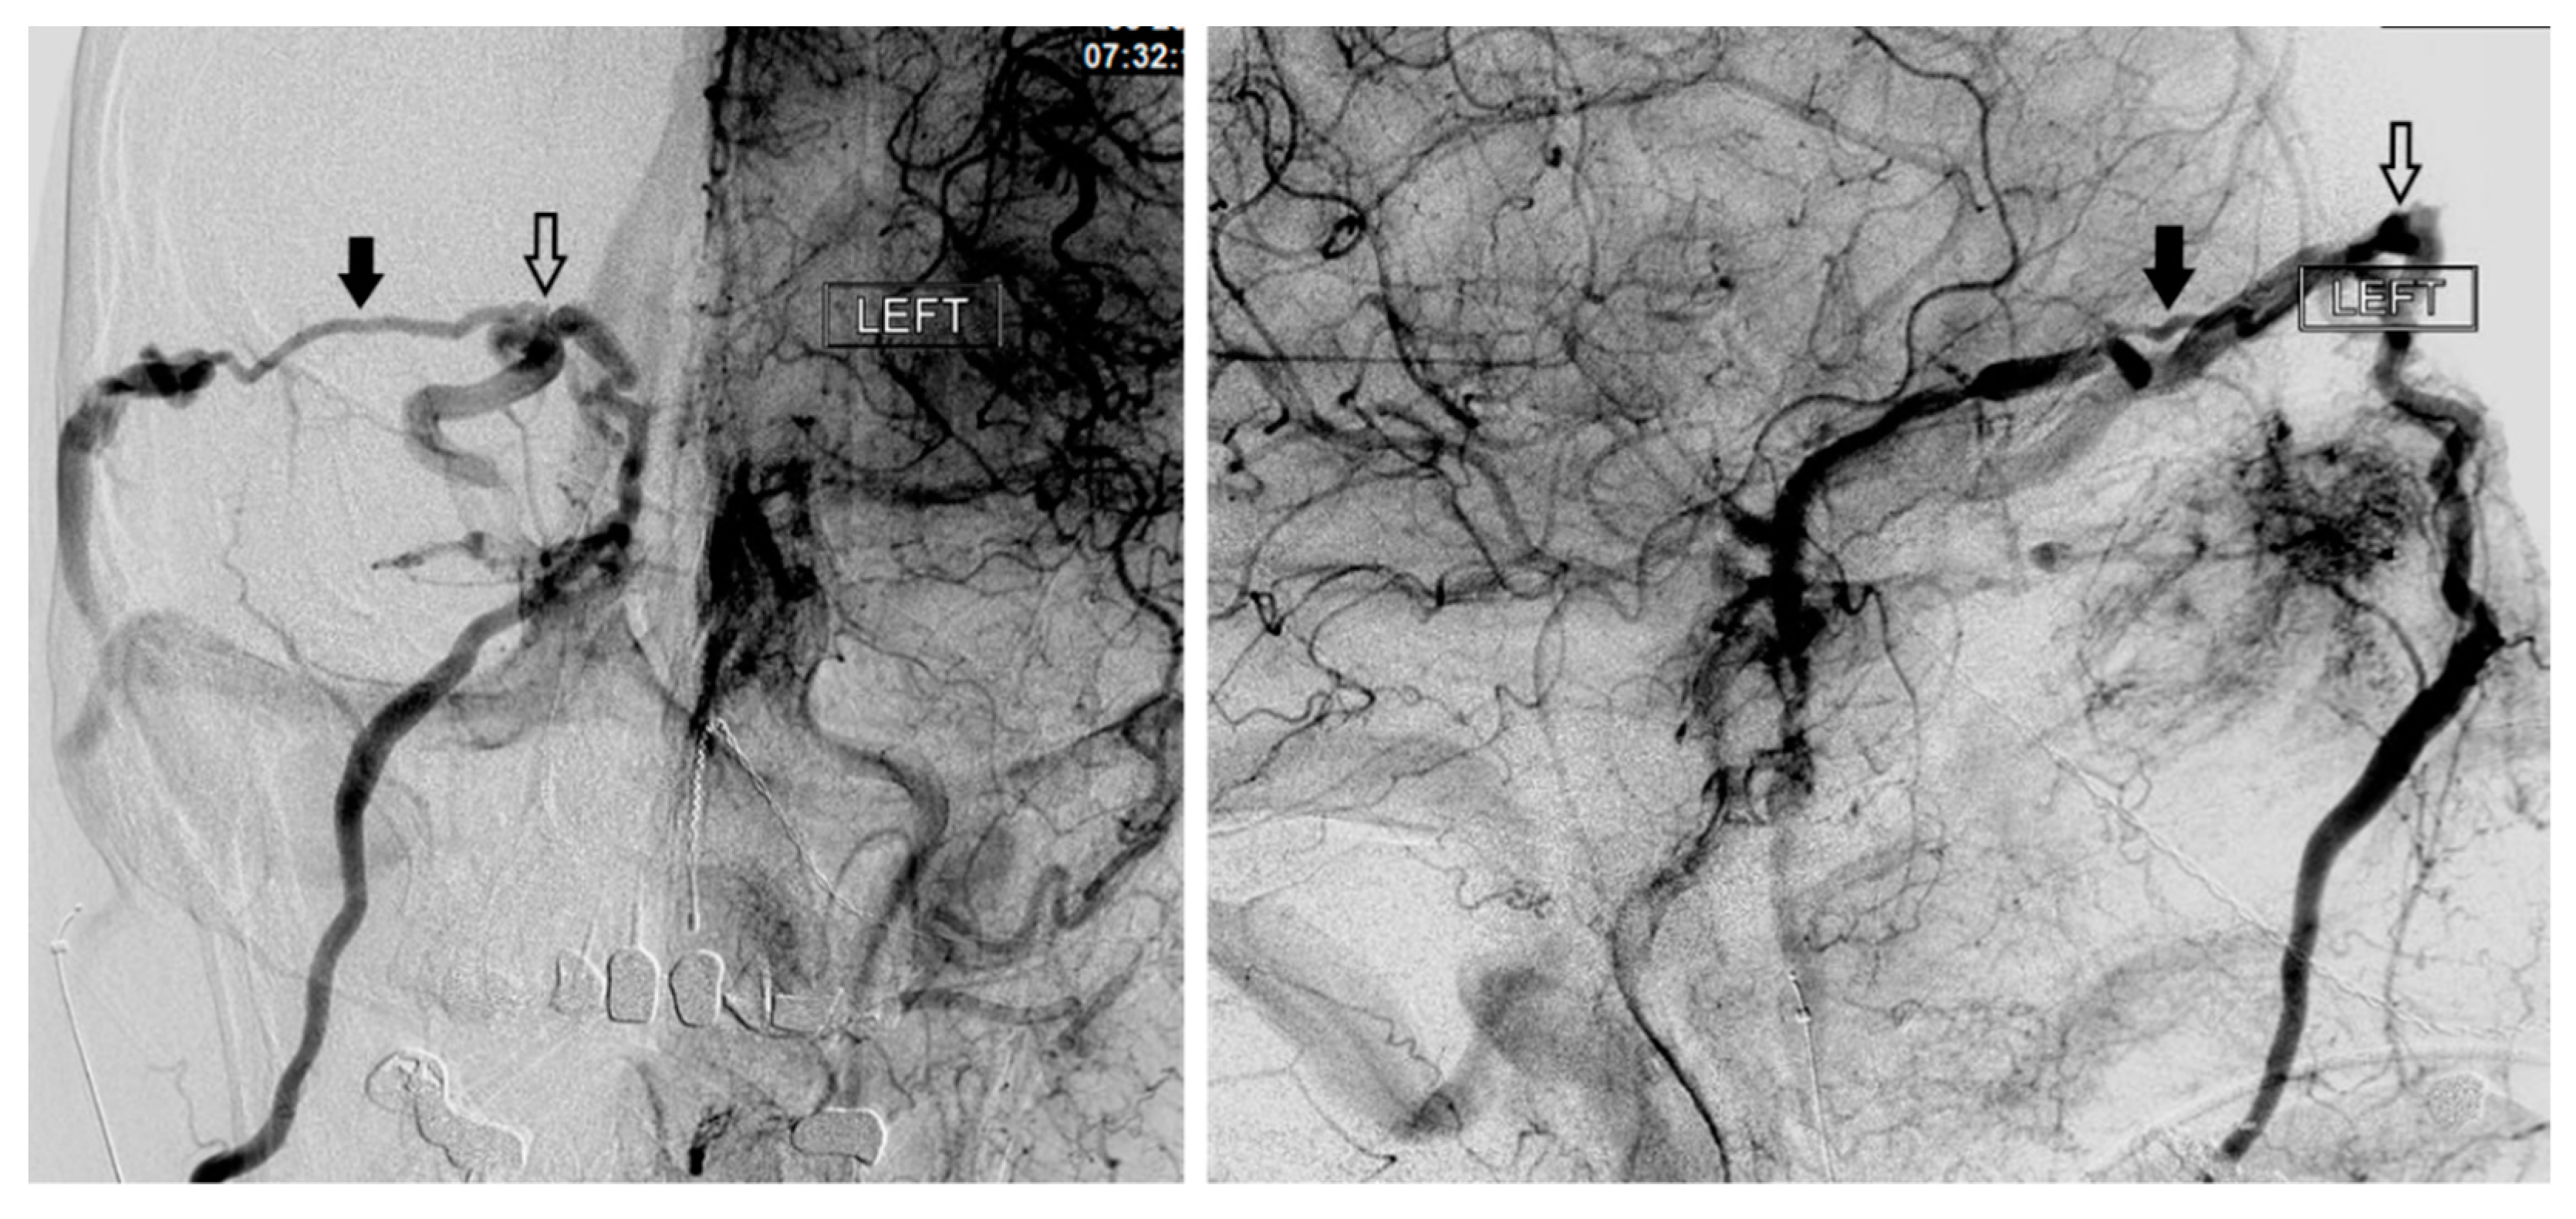

Figure 6. Demonstrates access of the left cavernous sinus (X) through an intercavernous approach (arrows).

In the setting of CCFs, the venous drainage may be primarily through contralateral pathways. Therefore, the best endovascular approach to a left sided CCF may be through the right IPS. Once the contralateral CS has been accessed, the ipsilateral CS can be accessed by crossing the intercavernous sinus, or more commonly through the clival plexus. The intercavernous connection is selected with a curved microwire directed either anteriorly or posteriorly. The microwire is then traversed across the intercavernous connection and, if necessary, looped within the opposite CS to provide support for the microcatheter to follow (Figure 6). This approach gives the operator the option of using virtually any of the described approaches on the contralateral side of the fistula site.